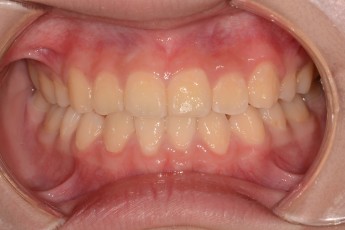

BEFORE & AFTER

- 덧니교정